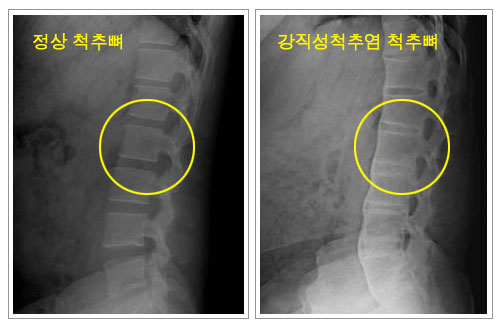

- 강직성 척추염

척추의 관절이나 인대가 점차 골화하여 굳는 만성 염증성 질환으로

남성에게 많으며 15-30세의 유전적 소인이 있는 사람에게 흔히 나타납니다. 건이나 인대가

닿는 부위인 섬유성 조직과 뼈조직과의 연결부에 염증이 생기면 섬유염이 생기고 다시 골미란을

일으켜 골화가 진행됩니다.

자연스럽게 진행이 멈추는 경우도 있으나 대부분 수년에서 수십년 걸쳐 서서히 진행되어 목에서부터

허리아래까지 굳어지게 되는 경우가 많습니다. 증상은 하부요통에서 시작하며 초기엔 좌골신경통과

유사하나 대부분 신경증상을 동반하지는 않습니다. |

1)

진단

| |

- 단순 방사선

- HLA-B27 항원 혈액검사(일반인에게는 나타나지 않음) |